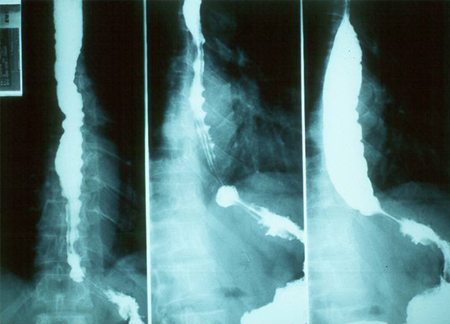

Barium swallow showing dilation of oesophagus

Grupo de Estudo em Correlalacao Anatomo-Clinica, Clínica Médica, Pontificia Universidade Catolica de Campinas, Sao Paulo, Brazil; used with permission